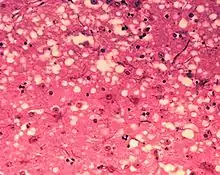

![]() Гистологический препарат — ткань лобной доли головного мозга больного болезнью Крейтцфельдта — Якоба | |

Прионы вызывают нейродегенеративные заболевания, так как образуют внеклеточные скопления в центральной нервной системе и формируют амилоидные бляшки, которые разрушают нормальную структуру ткани. Разрушение характеризуется образованием «дыр» (полостей) в ткани, и ткань принимает губчатую структуру из-за формирования вакуолей в нейронах[65]. Другие наблюдаемые при этом гистологические изменения — астроглиоз (увеличение численности астроцитов из-за разрушения близлежащих нейронов) и отсутствие воспалительных реакций[66]. Хотя инкубационный период прионных заболеваний, как правило, очень долог, после появления симптомов болезнь прогрессирует быстро, приводя к разрушению мозга и смерти[67]. Проявляющимися при этом нейродегенеративными симптомами могут быть конвульсии, деменция, атаксия (расстройство координации движений), поведенческие и личностные изменения.